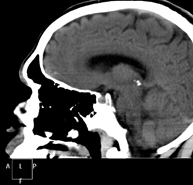

- TC Cráneo

Prueba radiológica que consiste en obtener imágenes del cráneo de alta definición anatómica (tronco cerebral, cerebelo, cerebro, calota craneal, etc.), mediante el empleo de un equipo de TC (Tomografía Computarizada).Indicaciones: traumatismos, cefalea, trastornos de la memoria, pérdida de fuerza súbita en una extremidad o mitad del cuerpo. - TC Cuello